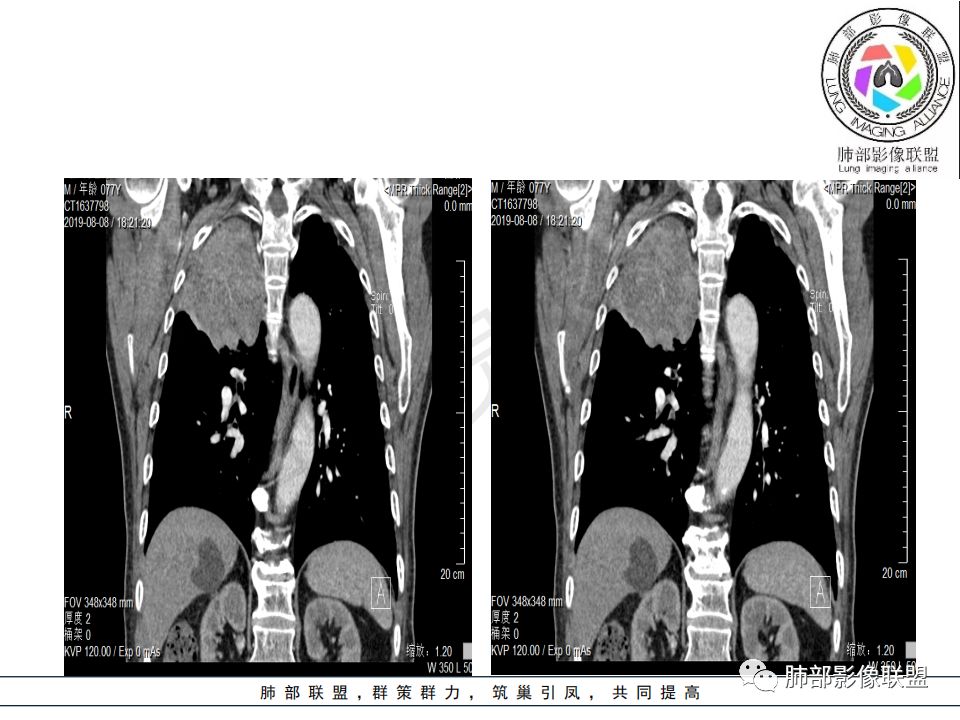

病史:男.77岁,咳嗽1月;干咳,少许白痰,无发热,2013胃癌术后,角蛋白24.65(0-3.07),SCC和proGRP不高;

影像:影像右侧大支气管阻塞,临床没有症状或很轻微,要想到胃腺癌转移;胸壁代偿好,透亮度稍低不明显,慢性过程;34.8-52.5HU,主病灶支气管前壁另有1结节,都做成增强两期了,动脉期较平扫有强化;

诊断:多发,转移,无淋巴结及胸腔积液;

鉴别:原发鳞癌。

晨读:患者老年男性,以咳嗽一月就诊,少量白痰,胸CT:纵隔右移,右肺体积缩小,气管下段管壁可见结节样改变,气管软骨变形,气管下段及右主支气管可见新生物向管壁浸润,并向管腔外生长,右上肺肺不张,但不张边缘可见病灶呈膨胀性生长,可见分叶,增强后强化明显。考虑:肺部恶性病变(鳞癌?)

从强化情况和冠状位看主要还是从外向内的一个肿块,有不张,但不张范围不大,近端支气管堵塞,考虑腺癌或类癌(原发或转移都可能),鉴别鳞癌。